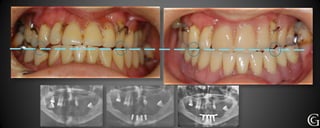

Prótesis Implanto Asistida

Las prótesis implanto asistidas, son restauraciones que utilizan los implantes

para retenerse y/o apoyarse. Los implantes sirven para reemplazar la raíz

del diente dentro del hueso, luego se realizará la restauración necesarias

(coronas, puentes, prótesis parciales o totales)

Técn. R. Schaeffer

Técn. S. Pacchioni y equipo

Prótesis Implanto Asistida Lasprótesis implanto asistidas, son restauraciones que utilizan los implantes para retenerse y/o apoyarse. Los implantes sirven para reemplazar la raíz del diente dentro del hueso, luego se realizará la restauración necesarias (coronas, puentes, prótesis parciales o totales)